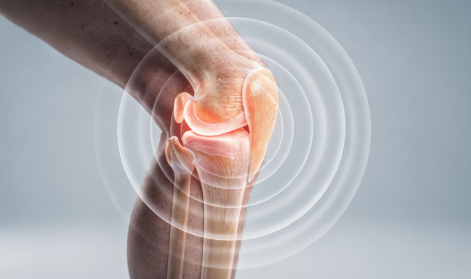

퇴행성 관절염에서 가장 먼저 느끼는 변화는 바로 통증입니다. 초기에는 특정 동작에서만 나타나지만 시간이 지나면서 통증의 빈도와 강도가 점점 증가합니다.

특히 계단을 오르내리거나 앉았다 일어날 때 무릎에서 찌릿한 느낌이 들 수 있습니다. “조금 쉬면 괜찮아지겠지”라는 생각으로 방치하는 경우가 많은데, 이런 반복이 관절 손상을 더 악화시킬 수 있습니다.

후기에는 가만히 있어도 통증이 지속되는 경우가 있어 삶의 질을 크게 떨어뜨릴 수 있습니다.

4. 관절 부기와 열감

염증이 생기면 관절 부위가 붓고 따뜻하게 느껴질 수 있습니다. 특히 무릎 관절에서 이런 증상이 자주 나타납니다.